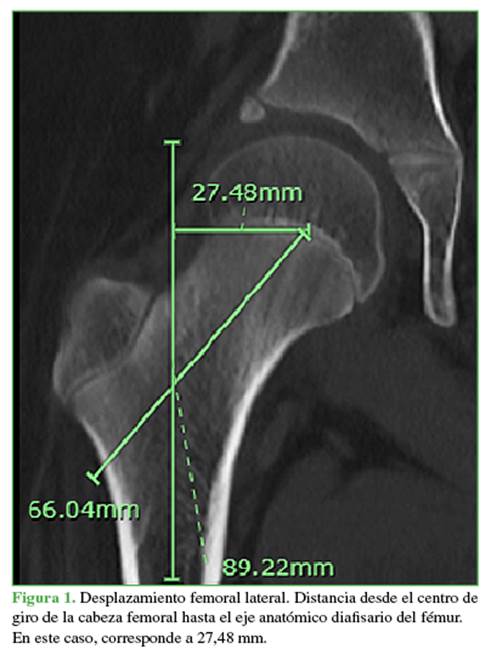

Para calcular el diámetro de la cabeza femoral en los niños >4 años, se midió la cuerda de mayor longitud contenida en la circunferencia de la cabeza y que pase por el centro de esta (Figura 4). En los pacientes de 4 años o menos, se midió el diámetro de la circunferencia completada a partir de los puntos de referencia descritos por Amador y cols.9

Para la medida del ángulo cervico-diafisario, se aplicó un suavizamiento de 0,6. Se encontró una disminución progresiva desde el nacimiento hasta los 10 años de 1,16° por año. Continúa disminuyendo 0,88° por año, entre los 10 y 12 años de vida, con un posterior aplanamiento de la curva entre los 12 y 16 años de edad (disminución 0,09°/ año) (Figura 7). El diámetro de la cabeza femoral tiene un aumento de 1,56 mm anual durante los primeros 13 años de vida, con un crecimiento más lento de 0,62 mm por año, de ahí en adelante (Figura 8).

En nuestra población, el desplazamiento aumentó con la edad, desde una medida promedio de 20 mm a los 5 años y hasta 37 mm a los 15 años (6 mm y 3 mm menos que la población de Szuper y cols., respectivamente). La longitud del cuello femoral tuvo un promedio de 33 mm a los 5 años y de 49 mm a los 15 años (1 mm y 1,5 mm, respectivamente, inferior a la población de Szuper y cols.). El tamaño de la cabeza femoral también fue menor que en la población comparada, con promedios de 24,6 mm a los 5 años y 38,2 mm a los 15 años (4 mm y 5,5 mm de diferencia, respectivamente). Estos cambios pueden estar relacionados con una talla más baja en nuestra población desde el nacimiento hasta la adultez comparada con la población húngara. La brecha encontrada disminuye progresivamente gracias a una mayor velocidad de incremento del desplazamiento y el tamaño de la cabeza femoral.